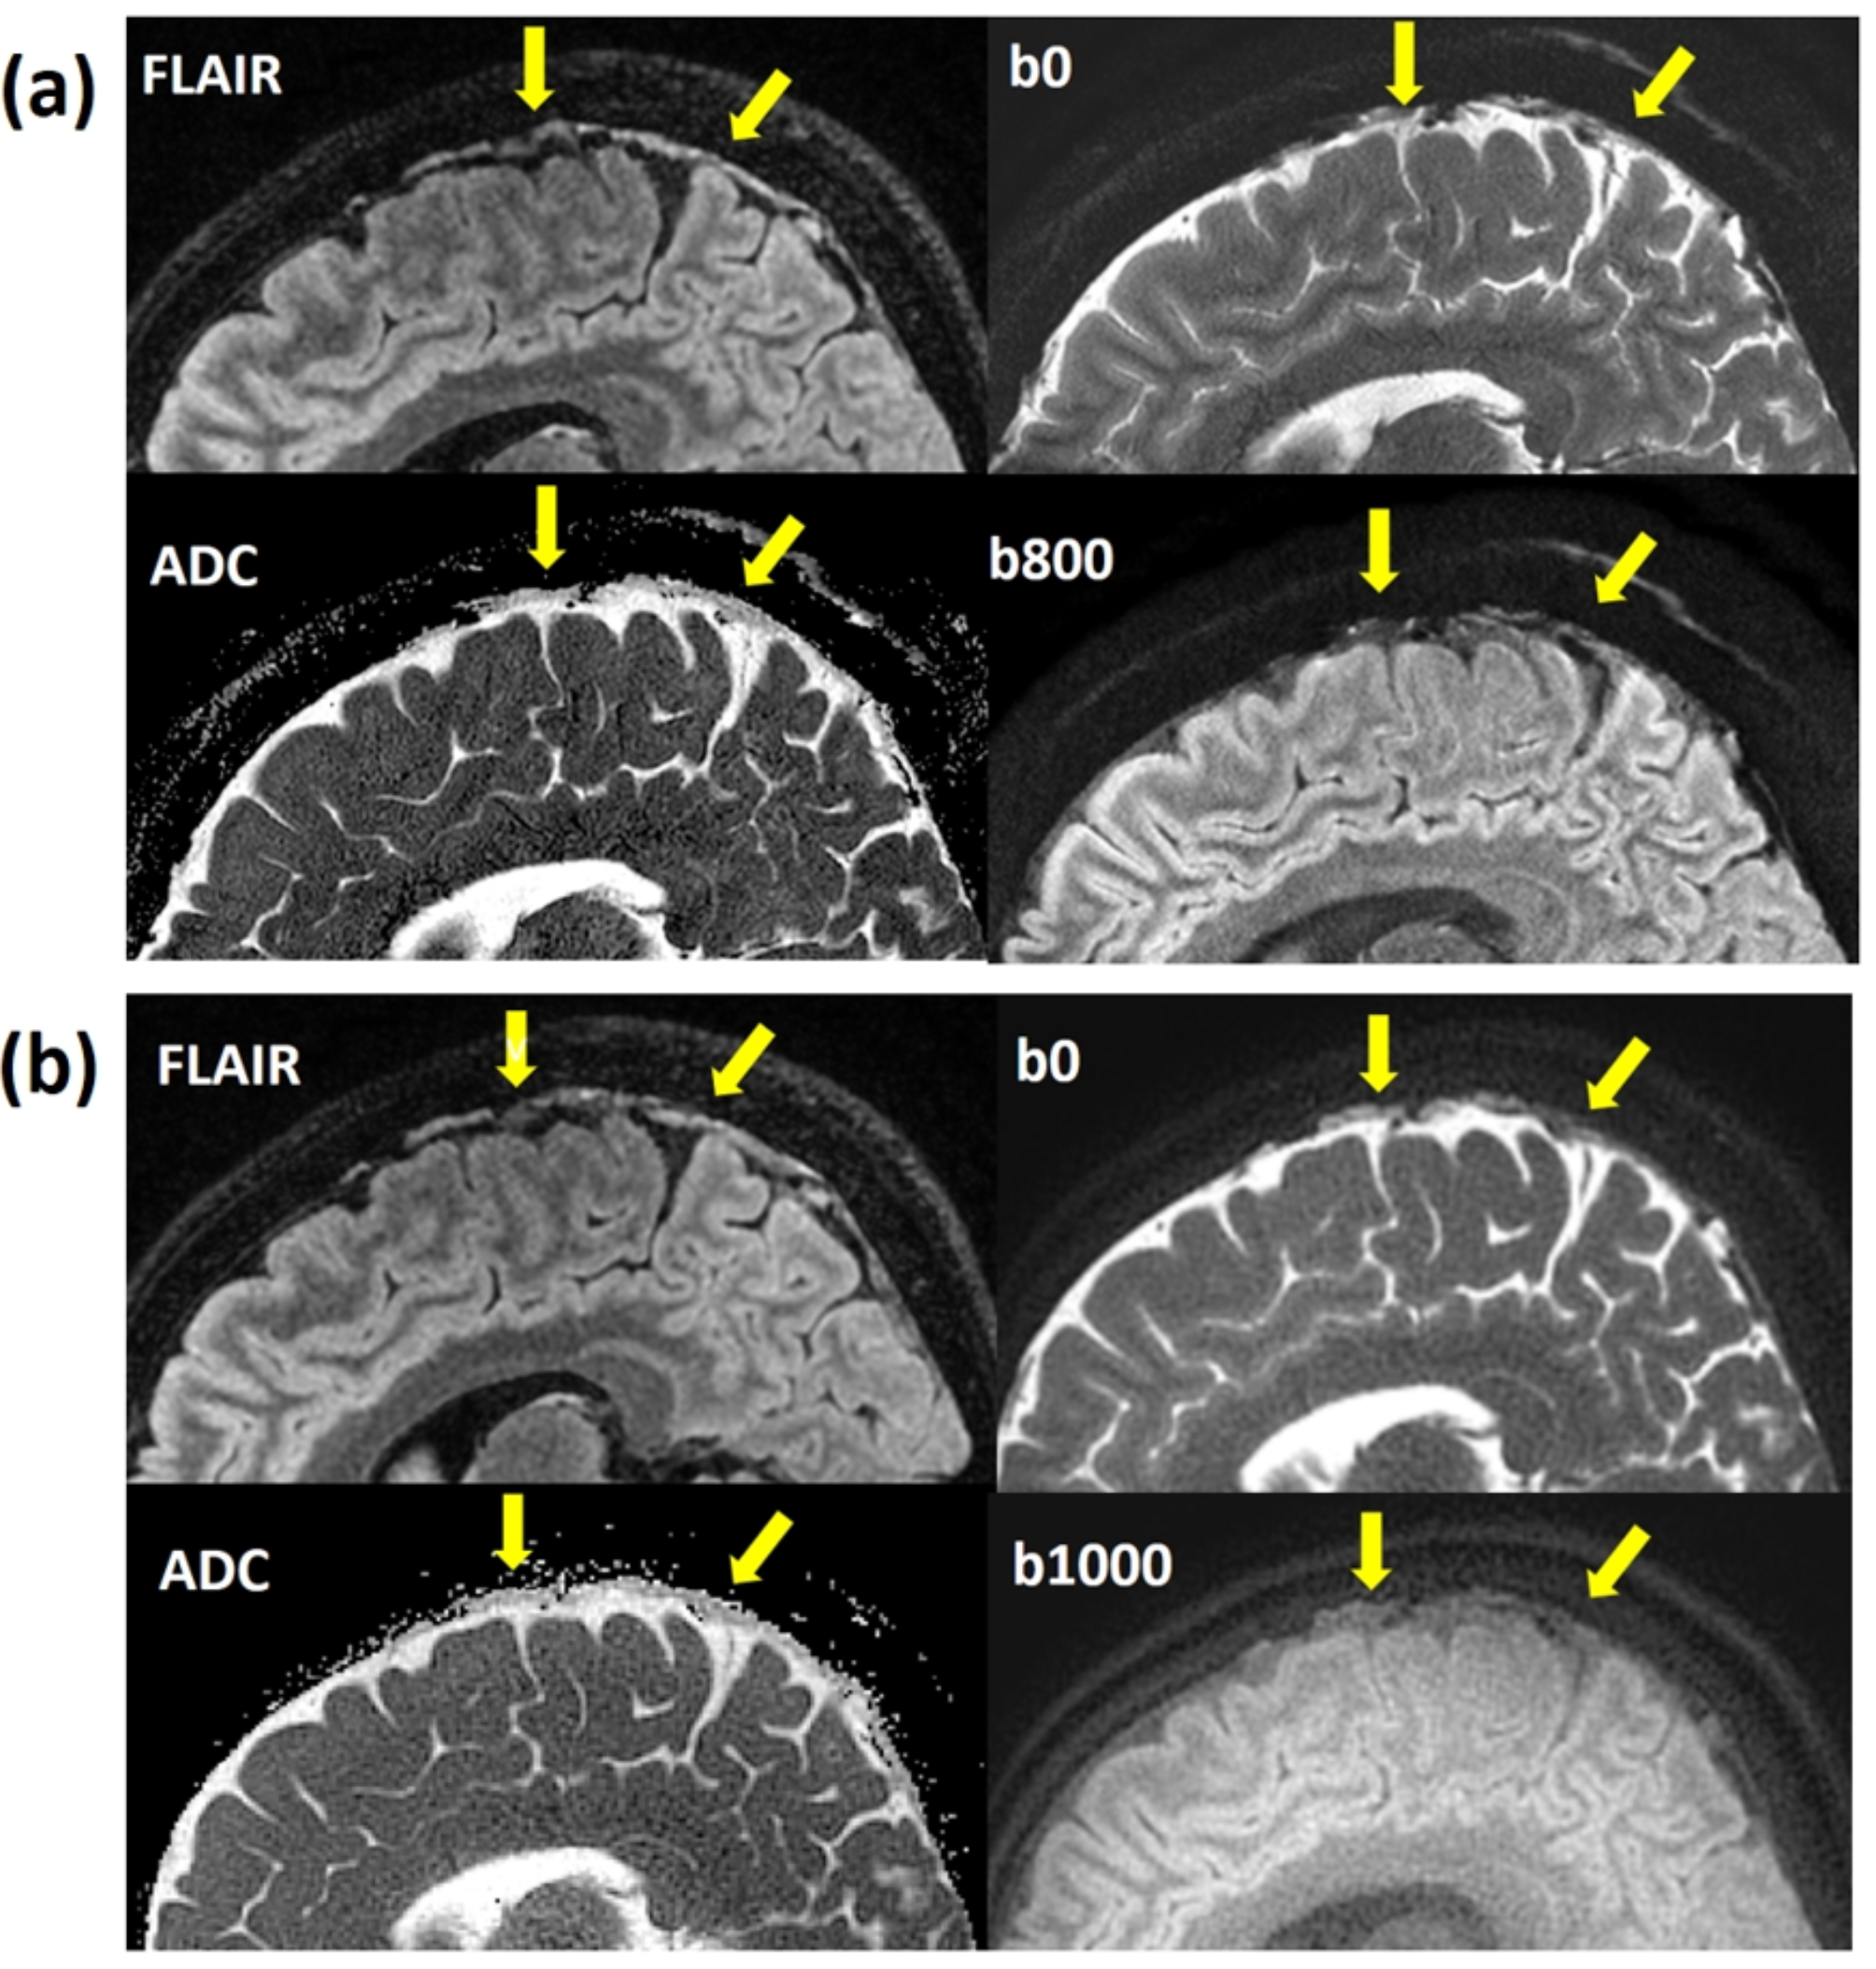

Fig. 2

(a) The sagittal view displayed the PSD on T2 FLAIR image (up left), MUSE DWI b0 (up right), MUSE DWI b800 (down right), and MUSE ADC map (down left) as indicated by arrows. (b) The sagittal view displayed the PSD on T2 FLAIR image (up left), PROPELLER DWI b0 (up right), PROPELLER DWI b1000 (down right), and PROPELLER ADC map (down left) as indicated by arrows. The ADC of the PSD appeared darker than that of the CSF.